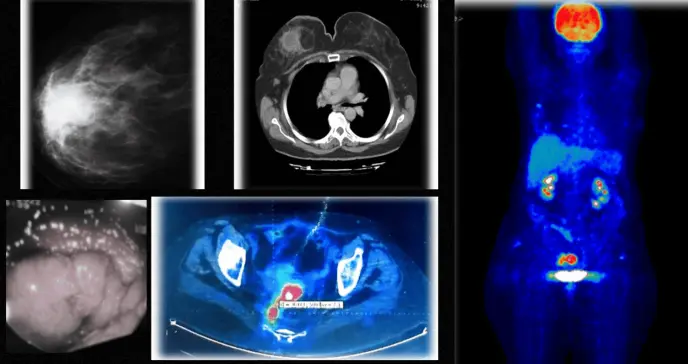

Los estudios imagenológicos confirmaron las sospechas: la mamografía mostró una masa lobulada con bordes espiculados y la tomografía computarizada reveló una lesión heterogénea de características sólido-quísticas de 5 × 4 cm localizada retroareolar, acompañada de adenopatías axilares ipsilaterales.

Mamografía que muestra opacidad espiculada en la mama derecha

Tomografía computarizada de tórax que muestra una masa en la mama derecha caracterizada por densidades heterogéneas.

Una tomografía por emisión de positrones revela una densidad en la cara lateral de la mama derecha, con captación marginal del trazador radiactivo, con un valor de captación estandarizado de 3,2. Además, se observan dos implantes pélvicos distintos.